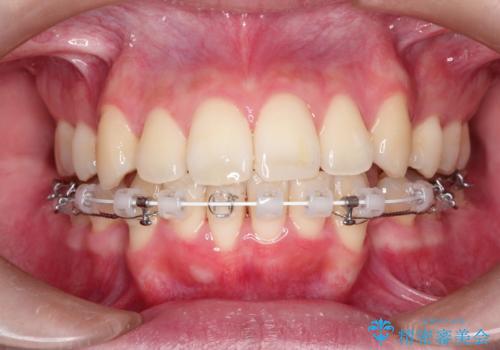

- 矯正装置

- ハーフリンガル

上下左右の前から4番目の歯を抜歯して、上下の前歯を後方に移動させる計画としました。